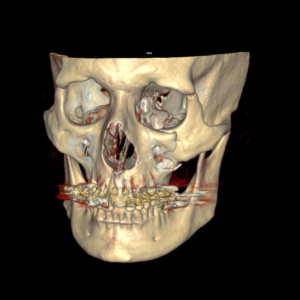

- Fraturas dos maxilares e órbita;

- Lesões craniofaciais (crânio, base do crânio e esqueleto facial);

A maioria dos ferimentos simples na pele pode ser tratada com anestesia local, limpeza da lesão e sutura. As fraturas da face e lesões complexas são tratadas sob anestesia geral. Os ossos quebrados são restaurados utilizando-se, geralmente, mini-placas e parafusos de titânio (que são biocompatíveis e não sofrem rejeição) que facilitam a recuperação e cicatrização óssea e dos tecidos